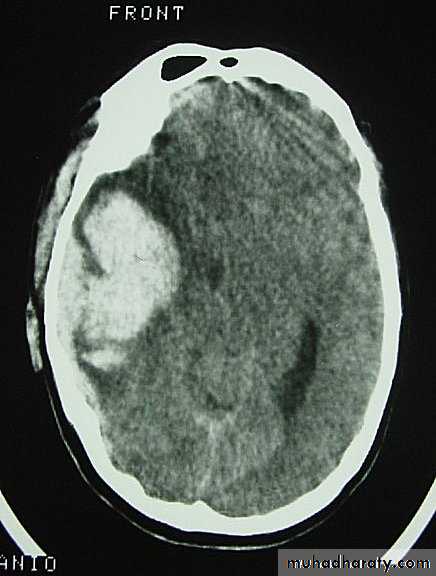

Acute Subdural Haematoma

Clinical Picture: patient will present with a picture similar to that of an extradural haematoma, but there is persistent loss of consciousness with no lucid interval.Ct scan will show a concave hyperdence collection because blood follows the subdural space over the convexity of the brain.

Acute Subdural Haematoma are rapidly evolving lesions and early evacuation via craniotomy is mandatory.